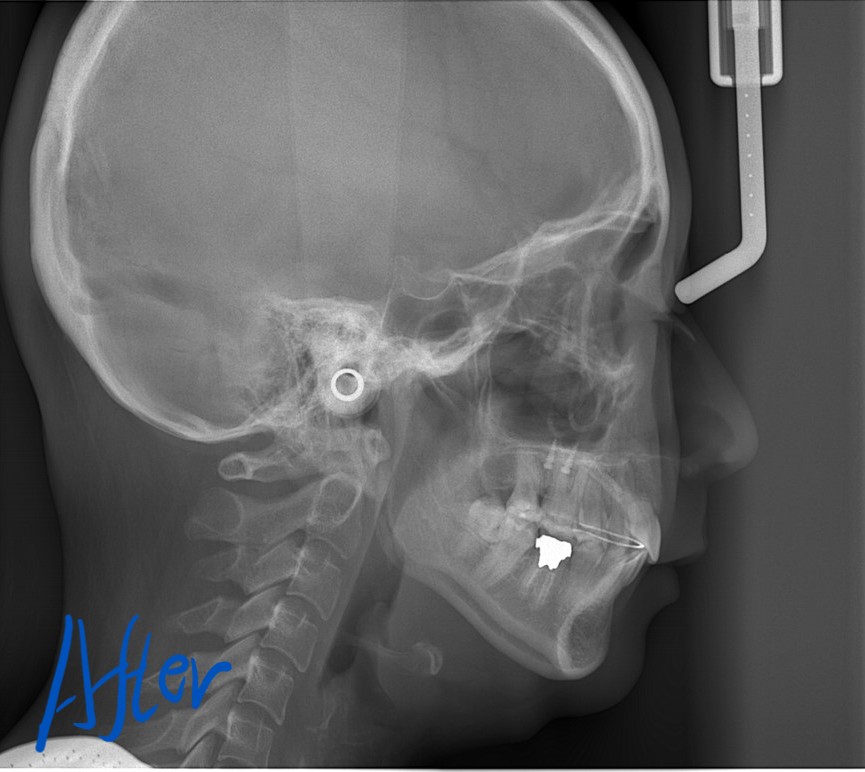

レントゲン写真でも比較してみましょう

左側が矯正治療前、右側が矯正治療後